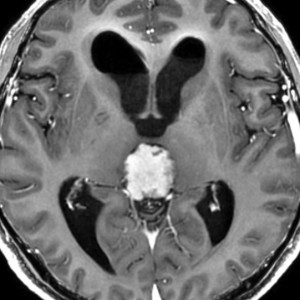

放射線化学療法後の画像です。腫瘍境界は不明瞭(左)で,腫瘍内出血(中央)して,左の視床に浸潤しています。かなりリスクは高いのですが,これを開頭手術で全摘出しました(右),この時点で完全寛解 CR です。この後にさらに化学療法と幹細胞移植(PBSCT,大量化学療法)が加えられました。